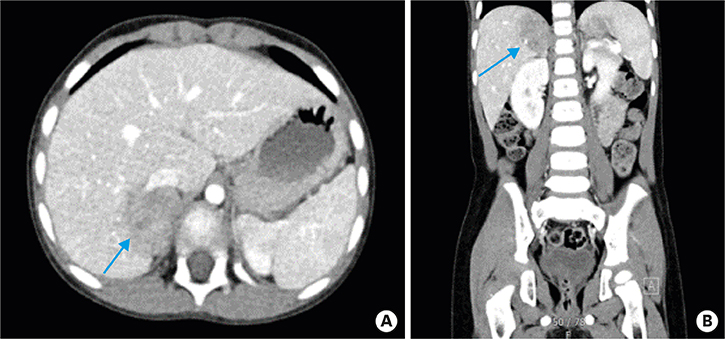

Abdominal-pelvic CT was performed on July 18, 2019, and it showed a low attenuated, ill-defined mass on the right adrenal gland, indicating a probable neurogenic tumor (Fig. 4). In addition, a metastatic lymph node (LN) along the anterior part of the right psoas muscle appeared suspicious. Multi-disciplinary teams discussed whether the anterior aspect of right the psoas muscle was a true metastatic lesion and made the decision to undergo an operation.

Fig. 4

Abdominal-pelvis computed tomography. An arterial phased axial view (A) and coronal view (B). The blue arrows show a low attenuated lobulated mass and tiny calcification at the medial portion.